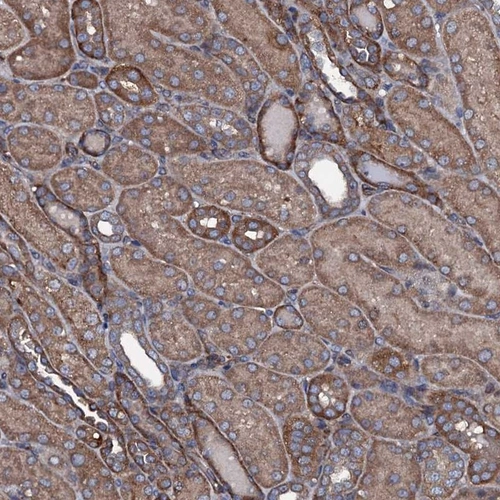

Immunohistochemical staining of human kidney shows cytoplamsic positivity in cells in tubules.